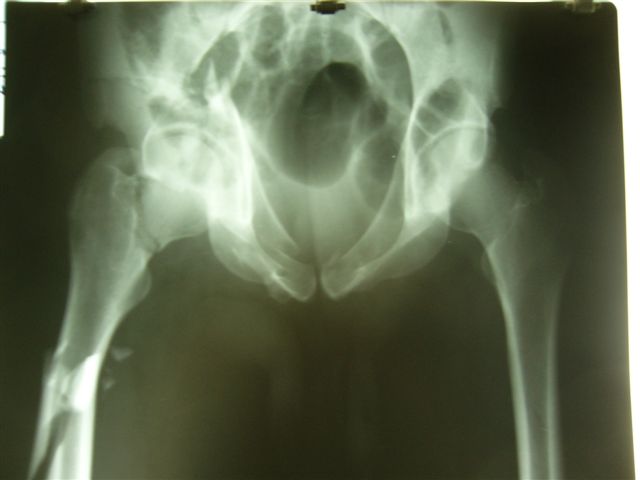

Уважаемые коллеги,Мужчина 36 лет от роду попал в ДТП 24.08.04 Рентгенограммы в приложении.

Диагноз- перелом с вовлечением таза, разрыв правого сакро-илиак сочленения vertical shear injury, перелом крыла подвздошной кости?, перелом ацетабулум Т type или Both column?, перелом шейки бедра, перелом проксимального отдела бедра.

перелом крыла правой подвздошной кости, перелом обеих колонн вертлужной впадины, двусторонний перелом лонных костей (С2.2) повреждение передних связок правого крестцово-подвздошного сочленения,

ипсилатеральный перелом шейки и диафиза бедра.